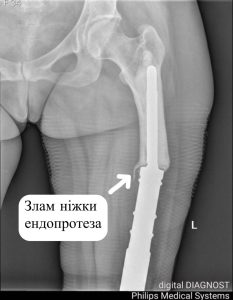

Ревізійне ендопротезування. Клінічний випадок. Ревізійне ендопротезування по праву вважається складнішим за первинне хірургічне втручання. Його проведення ускладнюється рубцевими змінами після...